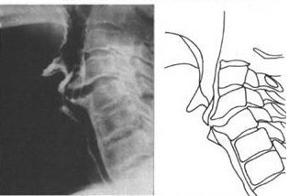

食管压迫型颈椎病 图1

321x416 - 17KB - JPEG

食管压迫型颈椎病 图2

340x492 - 20KB - JPEG